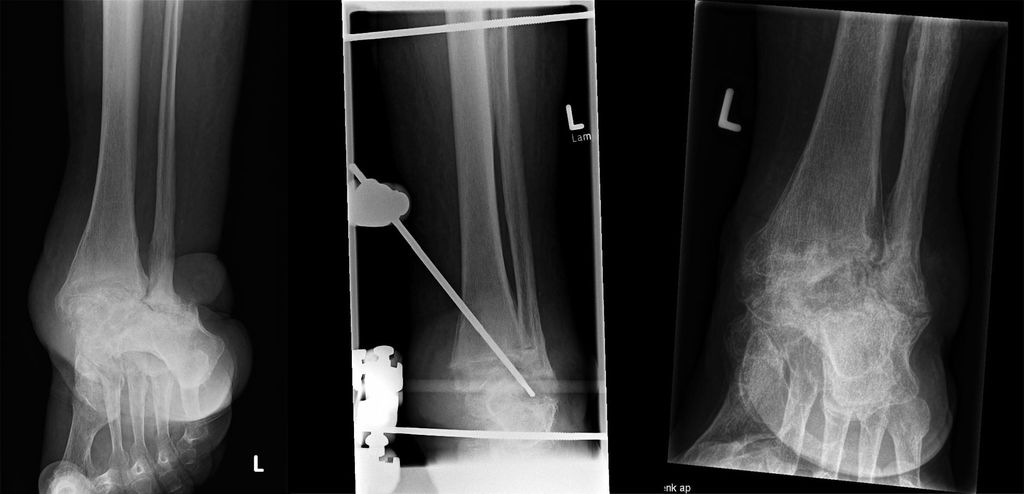

Die Standardbefestigungen des Kastenfixateurs können für die überwiegende Mehrheit der Fälle verwendet werden. Zwei selbstbohrende, parallele „full pins“ mit einem zentralen Gewinde werden in die proximale Tibia von medial nach lateral in der Frontalebene und parallel zum Boden eingesetzt. Dies ist eine sichere Zone, da das Gefäß-Nerven-Bündel weiter dorsal verläuft. Der Abstand zwischen den Pins wird durch die Klammer (Multi-Pin-Halter) bestimmt, die an beiden Seiten angebracht ist. Die Länge der Stifte beträgt in der Regel 250mm, bei sehr adipösen Patienten 300mm. Zwei kurze Verlängerungen an jeder Klemme in ventraler und dorsaler Richtung sind mit 4 (Karbon-)Stäben verbunden, die in Längsrichtung der Extremität ausgerichtet sind. Die Länge der dorsalen Stäbe beträgt in der Regel 300 oder 350mm, die der ventralen Stäbe 350 oder 400mm.

Eine stabile Fixierung des Fußes wird durch zwei weitere „full pins“ erreicht, von denen einer durch den Tuber calcanei und der zweite durch die distalen Mittelfußknochen (retrokapital) geführt wird, wo diese Knochen normalerweise in einer Ebene liegen. Während das Einsetzen des Fersenbein-Pins sicher und einfach ist, kann das Bohren des Mittelfuß-Pins durch alle 5 Knochen technisch anspruchsvoll sein. Im Gegenzug sorgen mehrere Corticales für eine ausgezeichnete Stabilität, sodass die Fixierung des ersten Strahls zusammen mit zwei kleinen Mittelfußknochen eine zufriedenstellende Fixierung bietet; ein oder zwei zusätzliche Knochen verbessern die Steifigkeit. Zwei Stangen, in der Regel 300mm lang, sind an den beiden Fußstiften befestigt. Ein Verbindungssteg unterhalb der Ferse ergibt zusammen mit den Stegen an beiden Seiten des Fußes die Form eines „U“. Die Verbindung der 4Tibiastäbe mit dem Pedal-U-Rahmen führt schließlich zu einer Box-Konfiguration, die in allen geometrischen Ebenen den gleichen Widerstand gegen Verformung bietet.

Durch die Verwendung desselben Satzes von Stiften, Stäben und Klammern bietet das Box-Frame-Design Anpassungsmöglichkeiten für die Rekonstruktion des Mittelfußes oder des Knöchels. Bei einem Charcot-Sprunggelenk ist der Fuß zunächst in seinem U-förmigen Rahmen fixiert. Gegenläufige Bewegungen der Stäbe auf beiden Seiten des Fußes ermöglichen die Supination oder Pronation des Vorfußes im Verhältnis zum Rückfuß. Danach wird der Fuß in die korrigierte Position manövriert. Außerdem kann eine Kompression erreicht werden, indem der Fuß-U-Rahmen proximal an den 4 Tibiastäben entlang nach proximal geschoben wird, bis eine (leichte) Biegung der Pedalstifte nach oben festgestellt wird. Die Kompression darf nicht übertrieben werden, um eine reversible, elastische Verformung der Pins, nicht aber eine irreversible plastische Verformung zu erreichen. Federstahl mit einer hohen Elastizitätsgrenze ist daher das optimale Pinmaterial.

Wenn das Lisfranc- oder das Chopart-Gelenk betroffen sind, sollte der Chirurg zunächst den Rückfuß stabilisieren und dann den Vorfuß ausrichten. Bei intaktem Sprunggelenk und Subtalargelenk wird der kalkaneare Pin an den beiden dorsalen Tibiastäben befestigt. Die Equinusdeformität im Sprunggelenk, die häufig mit der Charcot-Krankheit des Mittelfußes einhergeht, kann nun korrigiert werden, indem der Kalkaneus-Pin nach distal gezogen wird, mit oder ohne Verlängerung der Achillessehne, was zu einer Dorsalextension im Sprunggelenk führt. Auch hier gilt es, eine plastische Verformung des Stifts zu vermeiden. Der nächste Schritt ist das Bohren des Mittelfuß-Pins, der an den beiden ventralen Tibiastäben befestigt wird. Die beiden parallel zum Fuß verlaufenden Stäbe werden an den Tibiastäben befestigt. Schließlich wird der Stab unterhalb der Ferse mit den Fußstäben verbunden, sodass wieder die Form eines „U“ entsteht. Eine Kompression ist entlang der Fußschienen möglich, zusätzliche Apex-Pins mit distalem Gewinde, die die Fusionszone kreuzen, sind hilfreich, um die Kompressionskräfte zu bündeln, analog zum sogenannten Beaming-Konzept, und um eine Fragmenttranslation zu vermeiden.